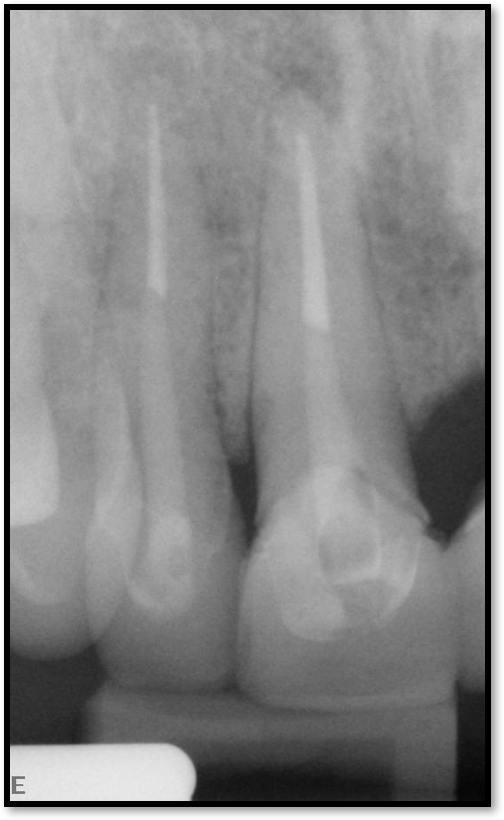

Figure 2 shows a situation where the clinician excavated the tooth of a patient with decay, and it pulped out. The buccal and lingual walls were intact; however, the walls were minimal, and there were still fragments of amalgam and cracks. If the clinician prepared this tooth after building it up, the clinician would lose all the good tooth structure that was left. This tooth would likely need a post.

Fig 2. Minimal walls.

Figure 2